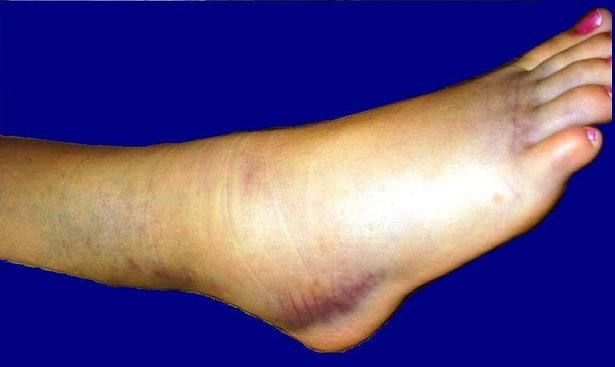

Общие симптомы для всех видов вывиха голеностопа – это боль, отек, деформация и невозможность выполнения им его основных функций. Обо всем и по порядку.

- Отек. Всегда носит прогрессирующий характер, распространяясь по всей окружности голеностопа, лодыжек, голени и стопы. Может возникать мгновенно в виде гематомы и синюшности кожи.

- Деформация сустава. Зависит от вида вывиха и степени смещения стопы относительно суставной вилки голени. При подвывихах видимой на глаз деформации не определяется. В случае полного вывиха стопа может быть полностью загнутой в ту или иную сторону.